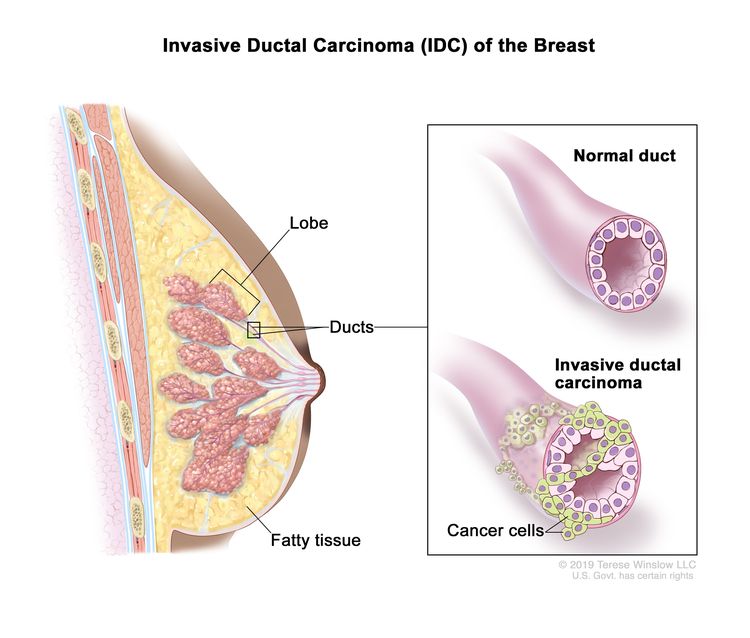

健康・医学 Breast Cancer Breast Cancer Treatment (PDQ®) - American Association forの詳細情報

Breast Cancer Treatment (PDQ®) - American Association for。nejmcpc2309499_f1.jpg。Frontiers | (KAUH-BCMD) dataset: advancing mammographic。乳がんに関する最新の情報を提供するモノグラフ。Breast cancer: Know the facts | CNN。病理学や治療法についての詳細な章を含む。。- タイトル: Breast Cancer- 編集者: B. Hoogstraten, I. Burn, H.J. G. Bloom- 出版社: Springer-Verlag- 内容: 乳がんに関する最新の情報を提供するモノグラフ- 特徴: 病理学、診断、治療法についての詳細な章を含む- シリーズ名: UICCご覧いただきありがとうございます。視能検査学。